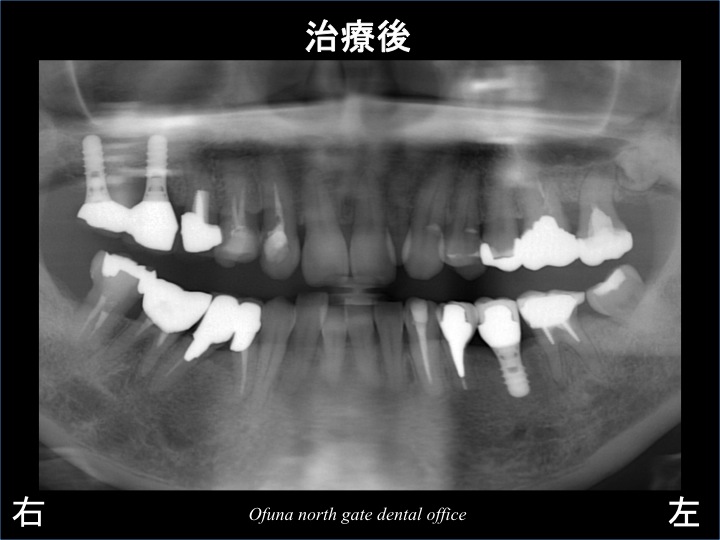

以下は、インプラント治療後のレントゲンになります。